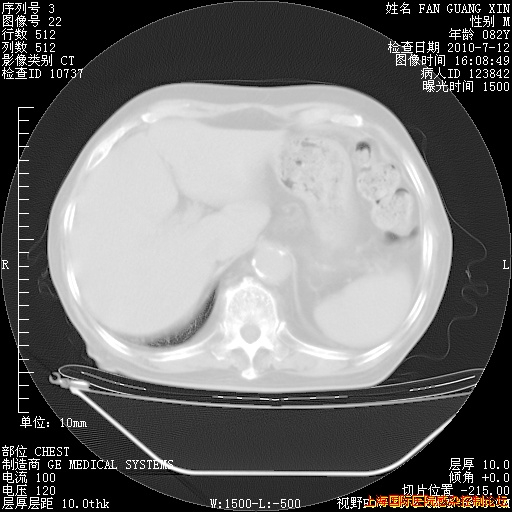

今天复查CT

今天CT

整整相隔30天的肺部CT好像有所好转啊。甲强龙减量第3天,需要观察体温。